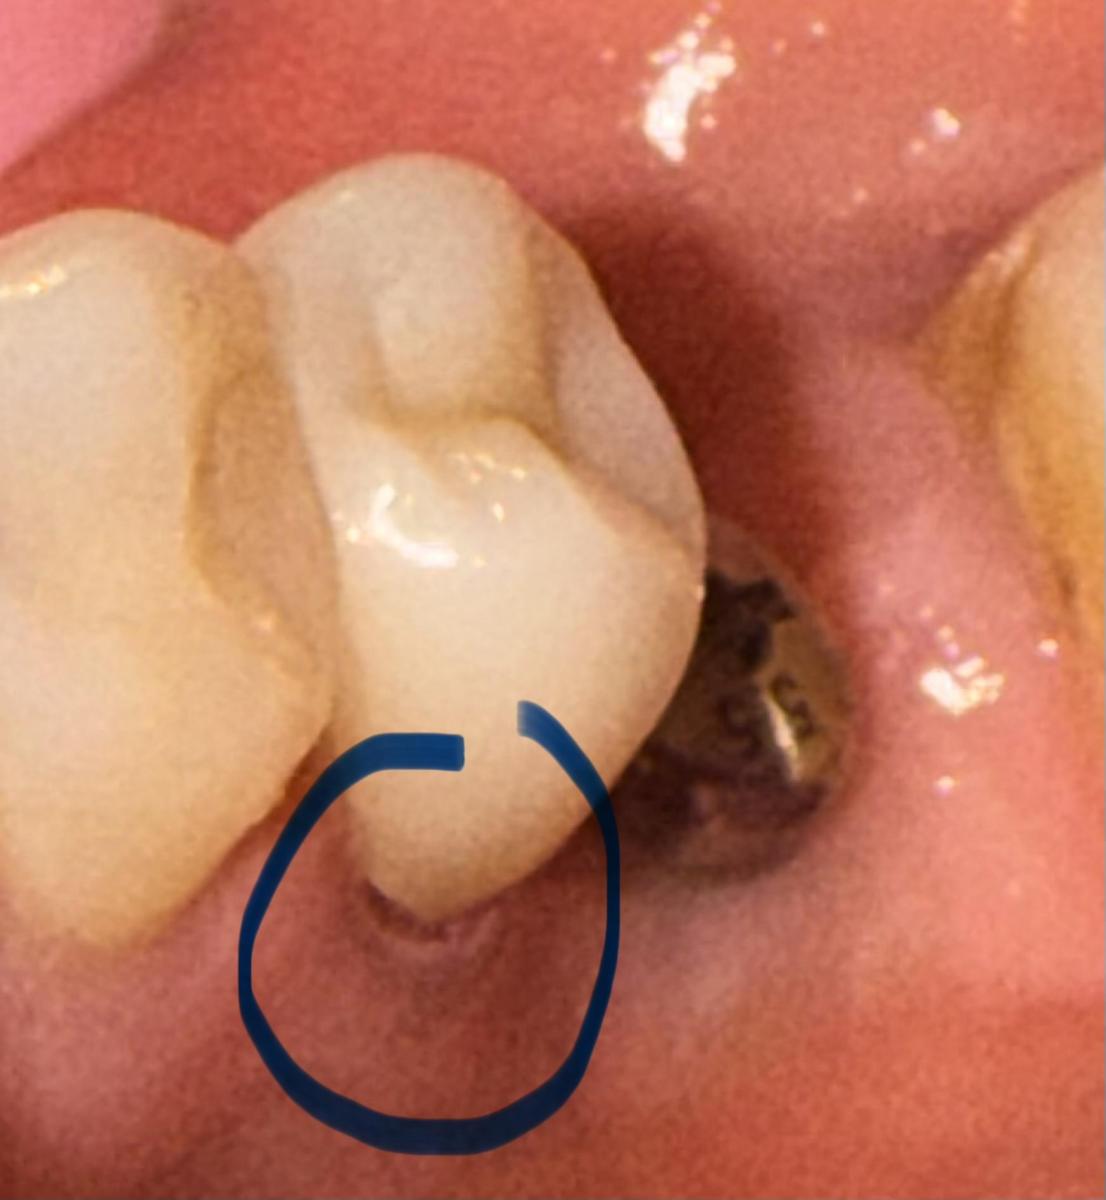

Вечером решила дома рассмотреть все внимательно и увидела, что с внутренней стороны есть небольшой зазор (1 мм примерно на вскидку). Не понимаю как врач этого не мог заметить?! Такое возможно? Или надеялся что я не увижу и потом скажут это у вас десна опустилась из за импланта.

Напишите, пожалуйста , что думаете. Интересно ваше мнение касательно работы врача. Сбоку (внешней стороны) все отлично.

Фото прикладываю.